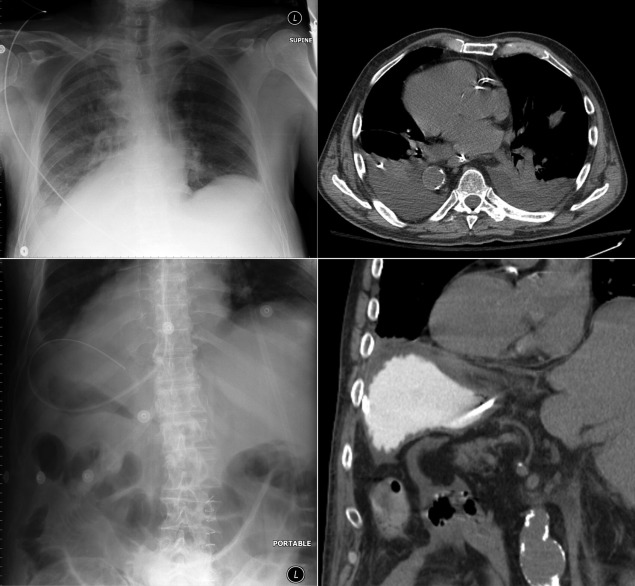

Situs refers to the position/arrangement of the thoracic and abdominal organs ( Figs 20-1 to 20-5 ). The posteroanterior/frontal chest radiograph is able to depict the location of the heart, the left ventricular apex, the aorta, and the gastric air bubble, and it may thereby determine situs.

Situs Ambiguous/Heterotaxy/Indeterminate Situs

The gastric air bubble and the aortic “knob” are on different sides; therefore, the situs is not predictable (“ambiguous”). Manifestations of ambiguous situs include the following:

Caval abnormalities

Inferior vena caval interruption with azygous continuation (nearly always)

Bilateral superior vena cava or inferior vena cava